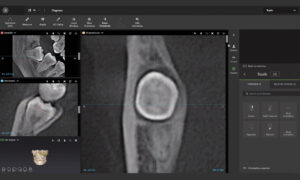

Our centre utilizes state-of-the-art 3D cone-beam CT (computed tomography) technology that provides highly accurate 3-D radiographic images for the diagnosis, planning and treatment of oral surgery.

This technology provides highly accurate 3D radiographic images for the diagnosis, planning and treatment of dental implantology, TMJ analysis, airway assessment, oral and orthognathic surgery and other dental procedures.

Undistorted, anatomically correct views of the jaws, teeth and facial bones along with cross-sectional (bucco-lingual), axial, coronal, sagittal, cephalometric and panoramic views are easily generated.